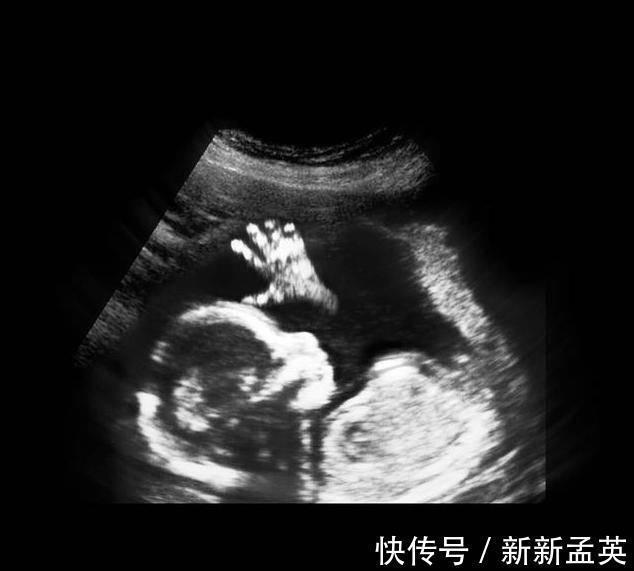

进入了16周,胎儿具备了很多本领,比如吞咽羊水、排出尿液、玩耍脐带、开始有了妈妈能够感受到的胎动,胎儿生殖器官的发育开始可见。

其实从孕9周开始,胎儿的性别就开始分化,孕17周,B超扫描清晰可见胎儿的性别,不过也有的宝宝因为胎位的原因,或者脐带遮挡,让医生产生了误判,男女会出现翻盘的可能呢。